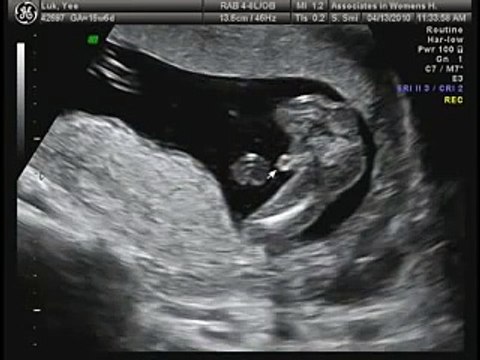

16 Weeks Pregnant Ultrasound Inside your 16 weeks pregnant belly baby is listening to your voice thanks to tiny bones forming in their ears. Youll probably have a four-month prenatal visit around the time youre 16 weeks pregnant.

At 16 weeks pregnant one would most likely feel that shes finally entered motherhood because she could now see the features of her baby through ultrasound scan and feel her inside her womb moving.

16 weeks pregnant ultrasound. The second trimester is often considered the best of the three as hopefully any early pregnancy symptoms will have subsided you might have more energy and even be lucky enough to get a lovely pregnancy glow. April 24 2019 April 25 2019 admin Health and Fitness. You are about four months into your pregnancy and you are probably looking pregnant by now.

In your 16-week pregnant ultrasound your doctor will probably be able to determine your babys gender. If you havent felt your babys little fluttering movements yet they could occur at any time now. Then theres your babys kick.

Twin Baby Shower Cake Baby Shower Cake Sayings. Once your OB sees a normal 16 weeks pregnant ultrasound your chance of miscarriage drops to only 1 percent. In the next few weeks your baby will double his weight and add inches to his length.

Your 16-week fetus is growing hair lashes and eyebrows and their taste buds are forming. And in happy news your risk of miscarriage is less than 1 after seeing a normal 16-week ultrasound. The movements of the baby can be felt like a light fluttering movement.